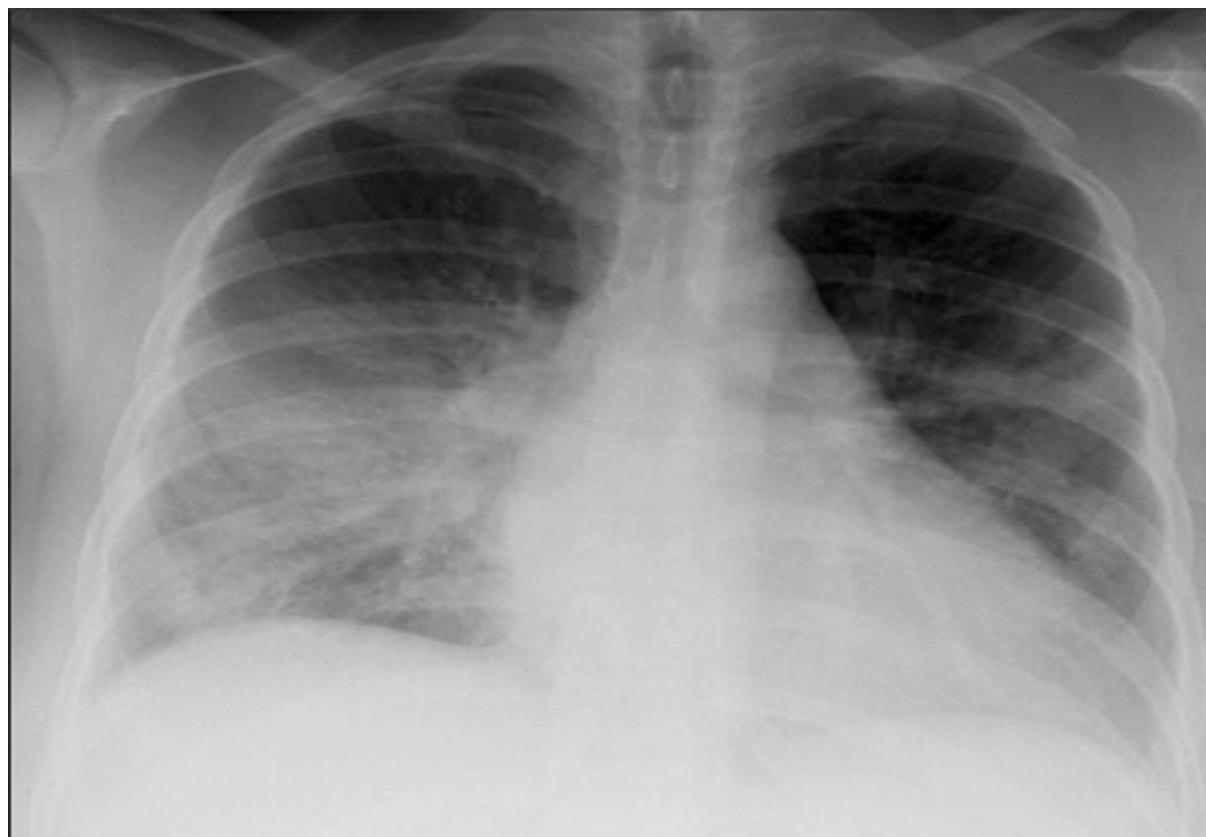

Pneumothorax

- Diagnosis: Right-sided Pneumothorax.

- Tension Pneumothorax (Clinical Diagnosis):

- Tracheal deviation to the opposite side.

- Hyperresonance on percussion.

- Congested neck veins, hemodynamic instability.

- Treatment of Tension Pneumothorax: Urgent needle decompression followed by chest tube insertion.

Pulmonary Edema

- Diagnosis: Pulmonary Edema.

- Radiological Signs:

- Cephalization (early).

- Kerley B lines, peribronchial cuffing.

- Bat wing or butterfly appearance (late/severe).

- Cardiomegaly.

- Differential Diagnosis: Pneumonia, ARDS.

- Management:

- Position: Sitting up.

- Respiratory support (CPAP or BiPAP).

- Diuretics (Furosemide), Vasodilators (Nitroglycerin).